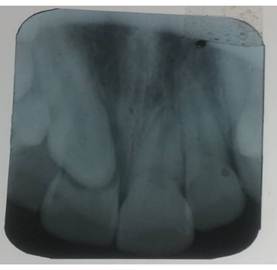

Se solicitó una radiografía periapical del sector anterior superior, la cual reveló un proceso de reabsorción radicular en el diente 11 (figura 1). Dicha reabsorción se atribuyó a la presencia del folículo dentario del canino incluido (13) en una posición ectópica, que desplazaba y afectaba a la raíz del incisivo.

Figura.1 Radiografía periapical del sector anterior superior.

En el paciente presentado, la radiografía periapical confirmó la pérdida de continuidad radicular del incisivo central (11), hallazgo que resultó determinante en la planificación del tratamiento.